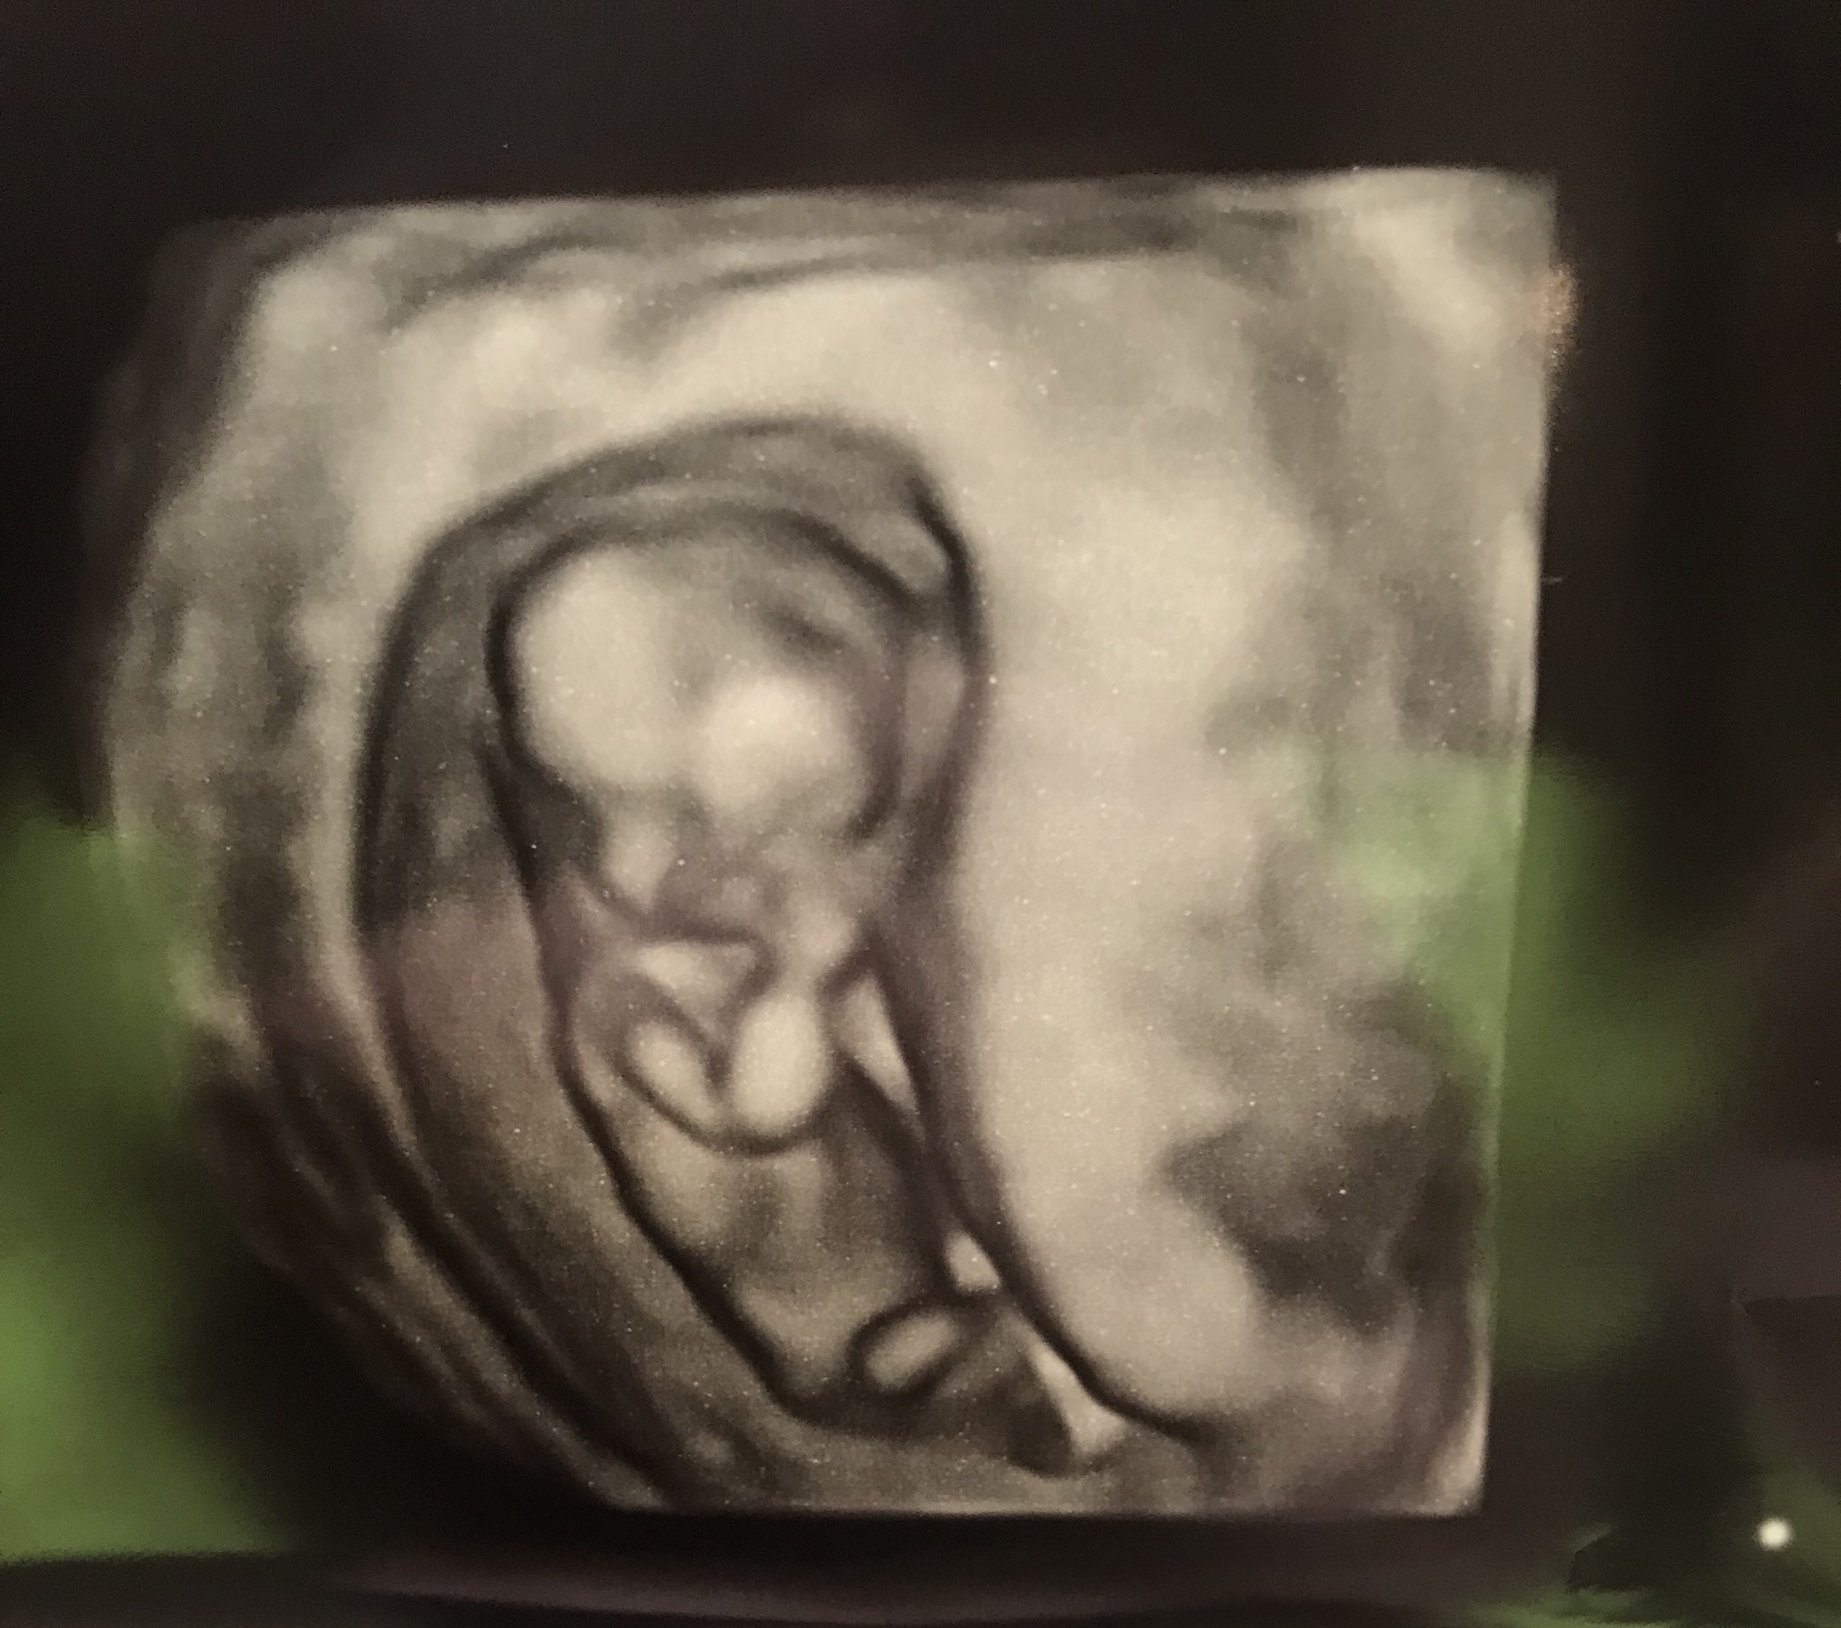

so everything is great! I actually feel fine and except for being super tired all the time, I feel pretty normal. Every ultrasound has looked great with the baby growing on track and a strong hb.

However, after today's US my PGAL brain has gone into overdrive. All the pictures look like the baby barely has any room in there. Like the sac is very small. The doctor didn't say anything about it. In fact, she look an extra amount of time to watch the baby's movement. I didn't notice it until I really looked at the pictures. Now, I am not sure if that is something I need to be concerned about. I can share a picture here just to show you what I mean. What do you ladies think?